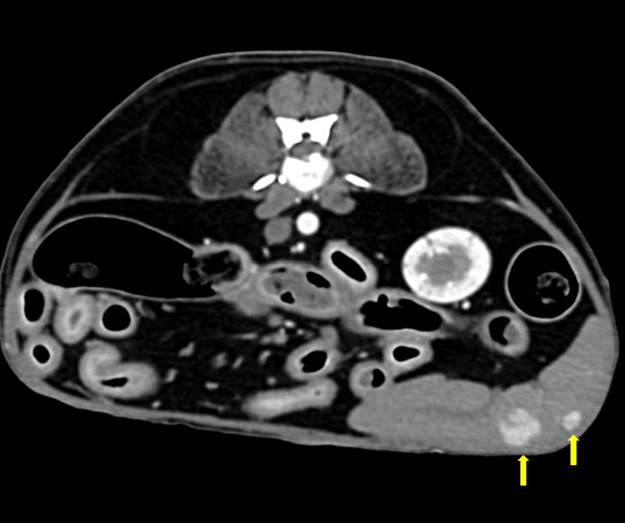

(๊ทธ๋ฆผ1. ์ธ์๋ฆฐ์ข

์์ฌ๋ณ๋ณ)